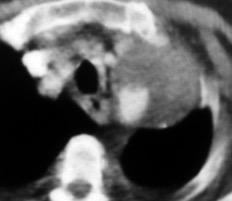

Marzo 2014: Perforación longitudinal distal secundaria a episodio de vómito (síndrome de Boerhaave). Derrame pleural izdo. que evoluciona a empiema.

Wang C-T et al. Tension hydropneumothorax in a Boerhaave syndrome patient: A case report . World J Emerg Med, 2021. Katabathina V et al. Nonvascular, nontraumatic mediastinal emergencies in adults:a comprehensive review of imaging findings. Radiographics. 2011.